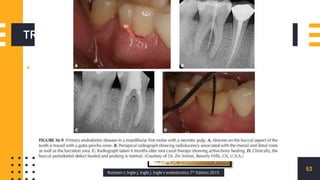

PRIMARY ENDODONTIC

LESIONS

DISEASE PROCESS

51

DIAGNOSIS

52

1

3

2

TREATMENT

▪ ENDODONTIC

53

Rotstein I, Ingle J, Ingle J. Ingle's endodontics 7th Edition 2019.